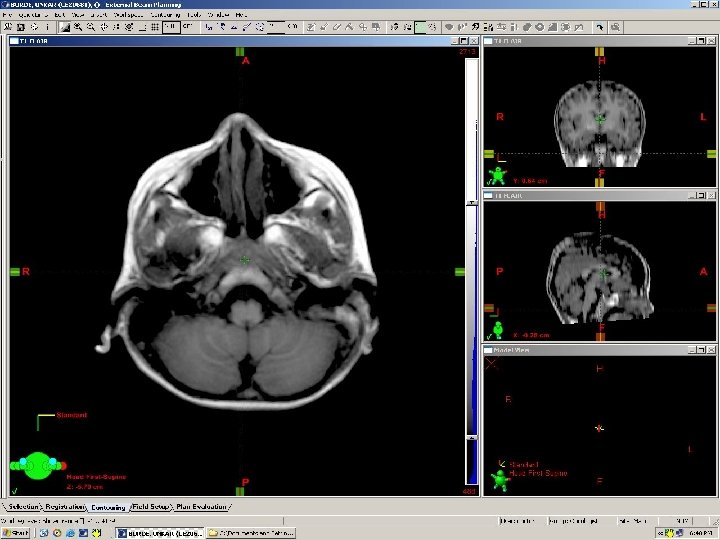

lens Eye ball Optic nerve Ethmoid air cells Temporal horn of lat ventricle Nasopharynx Internal carotid artery Inf. Temporal gyrus Inf pons Vermis Formation of Basilar artery Parieto occipital sulcus Transverse Sinus

Three-Dimensional Fast Spoiled Gradient-Recalled (3 D-SPGR) magnetic resonance imaging (MRI) Standard 1. 5 Tesla MRI Modified T 1 Post Contrast Contiguous Sections 2 mm – 1 mm thickness 256 x 256 grid